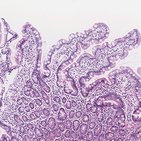

Digestive System

This custom quiz covers 174 structures across 15 topics, including: Stomach, Pancreas, Duodenum and 12 more!